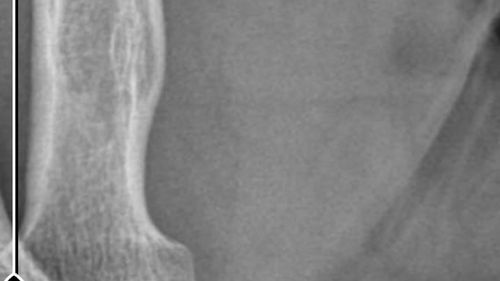

Olayın seyriİddiaya göre, 7 Haziran 2025 Kurban Bayramı'nda bıçak temizlerken sağ el başparmağını kesen Nurettin Güleryüz (34), ilk başvurusunu bir özel hastanenin acil servisine yaptı. Hastane tarafından pansuman yapılarak ve reçete verilerek taburcu edildiği, kanamanın devamı üzerine ertesi gün aynı…